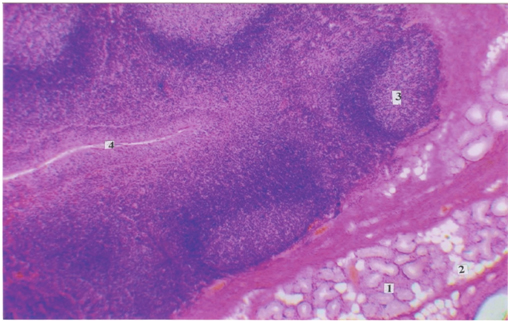

Статья имеет целью изучение железисто-лимфоидных взаимоотношений пищеварительного тракта в постнатальном онтогенезе и представляет особый интерес для клинической иммунологии. Макроскопическим и гистологическим методом нами исследованы слюнные железы, полученные от трупов 299 человек (язычные железы), начиная от новорожденных и до периода долгожительства, исследованы трупы представителей мужского и женского пола. Материал забирали в судебно-медицинских моргах Бюро СМЭ Департамента здравоохранения г. Москвы, что разрешено Постановлением Правительства РФ, Федеральный закон № 323, ст. 47, 4180-1, 355н. В фактический материал для исследования не включали случаи, когда при судебно-медицинском исследовании трупа выявляли патологические изменения пищеварительной системы. Микропрепараты (поперечные срезы) были окрашены гематоксилином-эозином и пикрофуксином по ван Гизону.

Малые слюнные железы, язычные и глоточные, располагаясь в толще языка и стенках глотки, выполняют важную эндокринную функцию – участвуют в обеспечении реакций местного иммунитета в ротовой полости. Множество публикаций посвящено регенеративным изменениям слизистой оболочки рта под действием секреторного иммуноглобулина А, который выполняет основную роль в регуляции местного иммунитета. В статье отражены важные аспекты возрастных изменений малых желез (язычных и глоточных). Характерная немногочисленность желез в детском возрасте обусловлена однотипностью питания в данном возрастном периоде, а снижение выработки секреторного иммуноглобулина А закономерно ведет к возникновению частых воспалительных процессов в полости рта и глотки. С возрастом устья желез расширяются и увеличивается их количество, что влечет за собой усиление местного иммунитета в ротовой полости и ротовой части глотки. Начиная с пожилого и старческого возраста наблюдаются инволютивные изменения, которые сопровождаются снижением выработки секреторного иммуноглобулина А и, соответственно, снижением показателей местного и гуморального иммунитета. Эти результаты полностью отражают топографические взаимоотношения желез с клетками лимфоидного ряда, и приведенные данные весьма актуальны для клинической иммунологии.